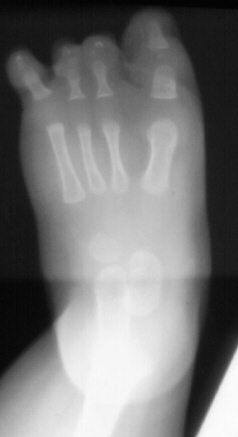

Foot

deformities are very commonly associated with PFFD.